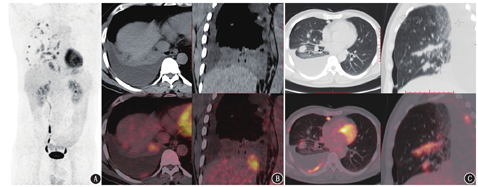

患者男,48岁,主诉咳嗽、咳痰1年余,肺部占位1周。2017年患者无明显诱因出现咳嗽,咳白色黏痰。2018年6月外院CT提示右肺下叶占位。入院体格检查右肺呼吸音消失。血红细胞沉降率54[正常参考值范围(下同):0~21] mm/1 h,糖类抗原(carbohydrate antigen, CA)72-4>300.00(0~6.9) kU/L,癌胚抗原12.69(0~5) μg/L。肺穿刺提示印戒细胞癌。胃镜检查阴性。为明确原发灶,行18F-FDG PET/CT(美国GE Discovery 710型)显像,结果示右肺多发类圆形或圆形密度增高影,最大者位于右肺下叶不张肺内,部分结节周围伴斑片及条索影,FDG摄取增高;右侧脏层及壁层胸膜结节状增厚,最大者位于右侧叶间裂,FDG摄取增高,考虑右下肺癌伴右肺及右侧胸膜转移(图1)。临床诊断为原发性肺印戒细胞癌。以"多西他赛(120 mg,第1天)+洛铂(50 mg,第1天)"化疗6周期后左肺进展,基因检测示间变性淋巴瘤激酶(anaplastic lymphoma kinase, ALK)突变,口服克唑替尼后部分缓解,随访36个月后失访。